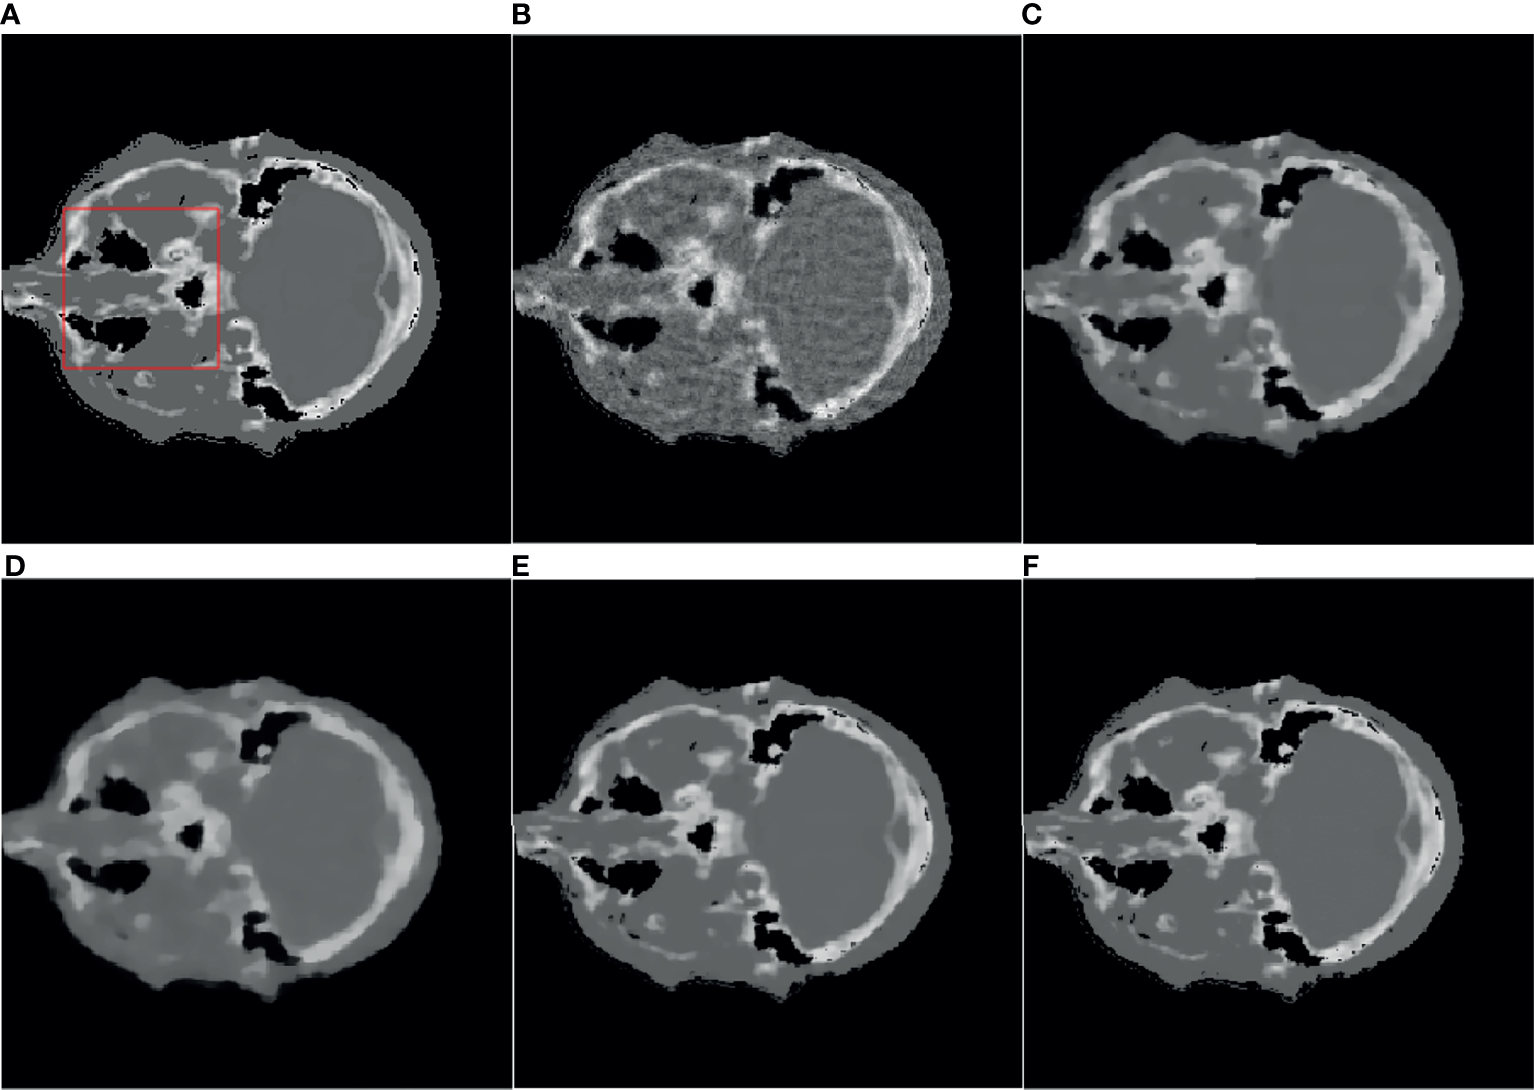

4.3 Actual Data Reconstruction

Figures 4, 5 are the reconstruction results of CBCT of the place that close to the center plane and bottom plane, respectively, it can be seen from Figure 4B that with the sparse angle projection, the reconstruction result of SART near the center plane still has serious artifacts. The reconstruction result of the SART-TV algorithm has a significant blocky effect, and many details are blurred. The reconstruction result of ASD-POCS algorithm is better than that of SART-TV reconstruction, but compared with the TpV minimization algorithm, the blocking effect is still more serious. The reconstruction result of the TpV-GIF algorithm not only suppresses artifacts as effectively as TpV, but also has better detail restoration, which can be seen in Figure 6.

Figure 6 ROI area enlarged image: the first row and the second row are the enlarged images of the red box area in Figure 4 and Figure 5, from left to right there are the reference image, SART, ASD-POCS, TpV and TpV- Reconstructed image of GIF. The (A–E) in this figure are correspond to the (A–E) in Figure 4 and Figure 5.

Observe the details indicated by the black and white arrows in Figure 6, and compared with the reference image, you can see that the ASD-POCS reconstruction result is relatively fuzzy, and details of the SART reconstruction image are more complete, but they all have serious artifacts. The details of the TpV reconstruction image are better preserved while the performance of TpV-GIF is even better. For the area indicated by the red arrow, the SART does not perform well in suppressing artifacts, the ASD-POCS blurs the details and has a blocky effect, on the contrary, TpV and TpV-GIF reconstruction results are better, the artifacts are suppressed while the edges are preserved.

From Figure 7, it can be seen that the SART reconstruction results are very smooth regardless of whether it is in a smooth area or an area where the voxel value changes greatly, so the edges and details may be blurred. The SART reconstruction result also changes seriously in the smooth area, which is reflected in the image as an artifact. TpV and TpV-GIF are relatively smooth in the smooth area, and change with the true value in the area where the voxel value changes greatly. The TpV-GIF curve is closest to the reference image curve, which means that the reconstruction result of the TpV-GIF algorithm is more accurate. Figure 8 shows the absolute difference between various reconstruction algorithms and the reference image. Obviously, the difference between the TpV-GIF reconstructed image and the reference image is smaller.